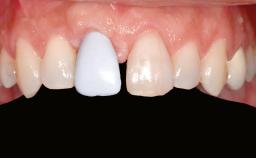

A 20-year-old woman was referred for implant therapy in 2004. Her medical history revealed no significant findings, and neither did she smoke nor take any medications. An extraoral examination revealed no abnormalities of the skin, hair or nails. The intraoral examination revealed only 11 permanent teeth clinically. These were normal in shape, size, and color. In addition, eight retained deciduous teeth (53, 62, 63, 71, 72, 73, 81, 82) were present. No abnormalities were detected during the general examination. The family history revealed that the patient’s father and two sisters were on record with similar conditions. The clinical examination revealed a thick gingival biotype. No recession of the attached gingiva was noted, but the retained deciduous teeth were mobile and unsightly. As a syndrome had not been diagnosed, the case was categorized as non-syndromic oligodontia.

Lip Line No exposure of papillae Exposure of papillae Full exposure of mucosa margin

Periodontal Phenotype Low-scalloped, thick Medium-scalloped, medium-thick High-scalloped, thin